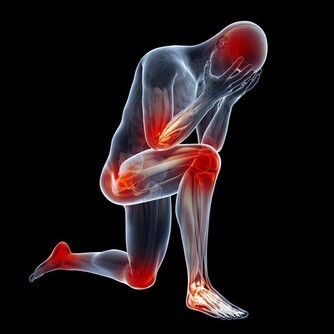

主要表現為不受控制地睡著,通常伴有猝倒、睡眠癱瘓、入睡前幻覺、夜間不安睡眠等。真可謂是嚴重干擾了人正常的工作生活,甚至還危及性命。